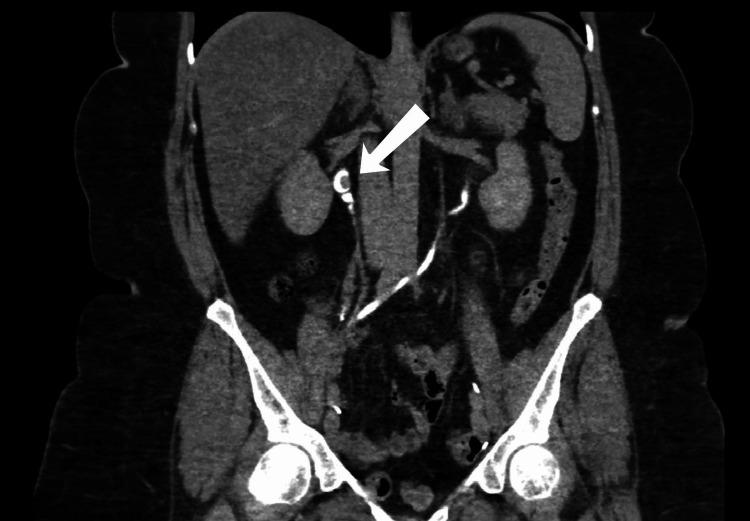

Bladder cancer is considered the most prevalent malignancy affecting the urinary tract system. Urothelial carcinoma, also known as transitional cell carcinoma (TCC), can arise from the entire urinary tract, with the bladder considered the primary site of origin and representing 95% of all cases. The management of TCC of the upper urinary tract is mainly by nephroureterectomy (NU). To our knowledge, there are no data regarding single-docking robotic-assisted NU following cystectomy with an ileal conduit. Therefore, in this study, we are reporting a case of single-docking robotic-assisted NU in a patient who previously underwent open cystectomy with an ileal conduit. A case of a 57-year-old female diagnosed with bladder cancer 10 years ago and underwent several transurethral resections of bladder tumor (TURBT) sessions presented for the first time in 2019, complaining of hematuria and dropping in the hemoglobin, which was not improving with multiple TURBT. For that, the patient underwent an open radical cystectomy with an ileal conduit. During the follow-up in 2021, computed tomography (CT) of the pelvis and abdomen with intravenous (IV) contrast showed a 7 mm enhancing lesion in the right proximal ureter, which was suspicious of proximal ureter mass. In 2022, the patient was again seen in the outpatient clinic; a CT of the pelvis and abdomen with IV contrast was done and demonstrated a significant progression of the mass size to 2 x 1.5 cm, with no other intraabdominal or intrathoracic lesions. For that, she underwent a single-docking robotic-assisted NU. To conclude, performing a single-docking robotic-assisted NU in a patient who previously underwent open radical cystectomy with an ileal conduit is challenging due to multiple adhesion and altered anatomy. More studies need to be published regarding the long-term outcomes of such procedures.

膀胱癌被认为是影响泌尿系统的最常见恶性肿瘤。尿路上皮癌,也称为移行细胞癌(TCC),可起源于整个尿路,膀胱被视为主要起源部位,占所有病例的95%。上尿路TCC的治疗主要通过肾输尿管切除术(NU)。据我们所知,尚无关于膀胱切除术后行回肠代膀胱术的单对接机器人辅助NU的数据。因此,在本研究中,我们报告了1例曾接受开放性膀胱切除术并行回肠代膀胱术的患者接受单对接机器人辅助NU的病例。1例57岁女性,10年前被诊断为膀胱癌,曾接受多次经尿道膀胱肿瘤切除术(TURBT),于2019年首次就诊,主诉血尿和血红蛋白下降,多次TURBT后病情未改善。为此,该患者接受了开放性根治性膀胱切除术并行回肠代膀胱术。在2021年的随访中,盆腔和腹部增强CT显示右近端输尿管有一个7mm的强化病变,怀疑为近端输尿管肿物。2022年,该患者再次到门诊就诊;进行了盆腔和腹部增强CT检查,结果显示肿物大小显著进展至2×1.5cm,无其他腹内或胸内病变。为此,她接受了单对接机器人辅助NU。总之,在既往接受过开放性根治性膀胱切除术并行回肠代膀胱术的患者中进行单对接机器人辅助NU具有挑战性,因为存在多处粘连和解剖结构改变。关于此类手术的长期结果,需要发表更多的研究。